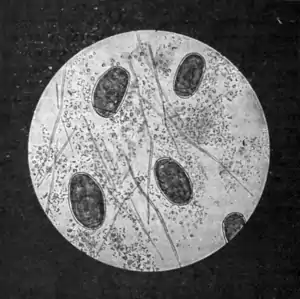

Fig. 161.—Ova of Paragonimus westermani in sputum.

which can be seen a number of tunnels filled with the same material that constitutes the characteristic sputum, and also containing one, two, or more small trematodes. The septa between the tunnels may break down and a considerable cavity be thus produced; and as this occurs in connection with one of the bronchi, with which the tunnels always communicate, it may give rise to the appearance of

a dilated bronchus. One burrow may communicate with another.